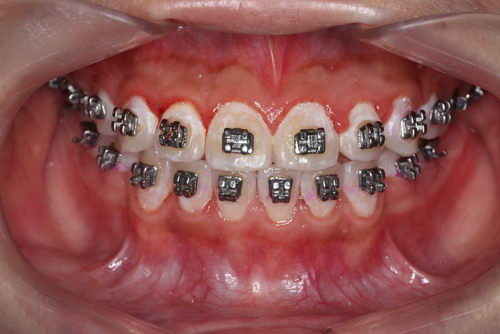

这是一位戴固定矫正装置的患者

第三张是使用邻面清洁工具之后,基本上是已经清洁干净了。